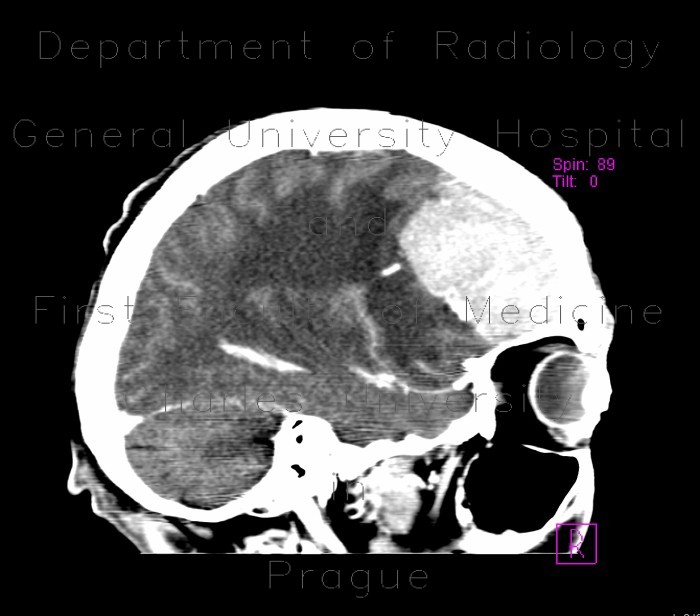

PhoTo quiz An Unusual Cause Of A Cerebral tumour In A Young ...

May 2006, Vol. 64, No. 5 ANswEr To PhoTo quiz (oN PAgE 152) AN uNusuAl CAusE of A CErEBrAl TuMour iN A YouNg PATiENT diAgNosis Based on cerebral and retinal vasculitis, cutaneous pustules, Turkish ancestry, and by exclusion of other possible causes, the ... Get Document